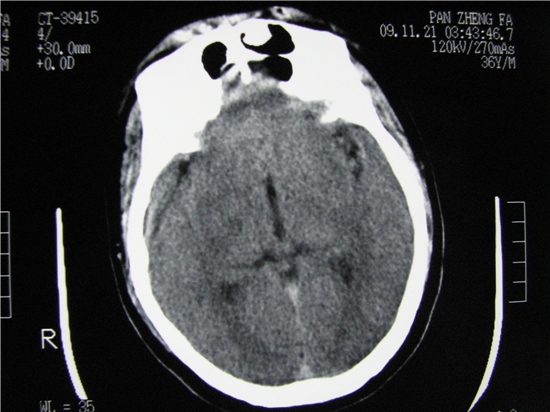

标题: CT23231:男 32岁 车祸伤,鼻腔内出血明显。 [打印本页]

标题: CT23231:男 32岁 车祸伤,鼻腔内出血明显。

额窦里是什么,骨窗怎么不清晰,是不窗宽窗位的事。

软组织及额窦内异物

额窦致密骨瘤,前额部及右顶部头皮损伤伴异物存留

左侧额骨、鼻骨骨折,头面部软组织肿胀。

左侧额骨、鼻骨骨折,额窦内的应该是游离骨块